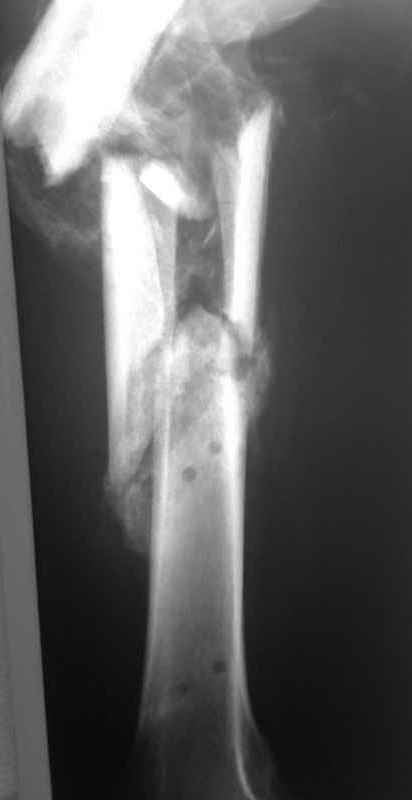

Re: Неправильно срастающийся оскольчатый перелом бедра

Конечно, снимки для планирования надо нормальные, не такой огрызок.

Можно закрыто мобилизовать отломки, наложить дистракционный аппарат, восстановить ось и длину, да и заштифтовать, на всякий случай с антибиотиковым цементным покрытием.

Спасибо за снимки. Предложения по тактике прежние.